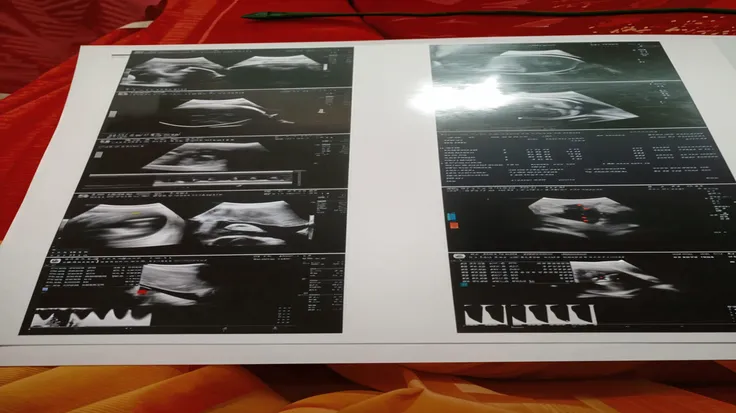

Image of a 10-week-old embryo in a uterus, captura, maternal photography 4 k

Image of a 10-week-old embryo in a uterus, captura, maternal photography 4 k, high quality scan, extremely high quality scan, high resolution scan,, video still, feto, webcam footage, high resolution scan, Escaneo profesional de alta calidad, metraje realista. hiper realista

Image of a 10-week-old embryo in a uterus